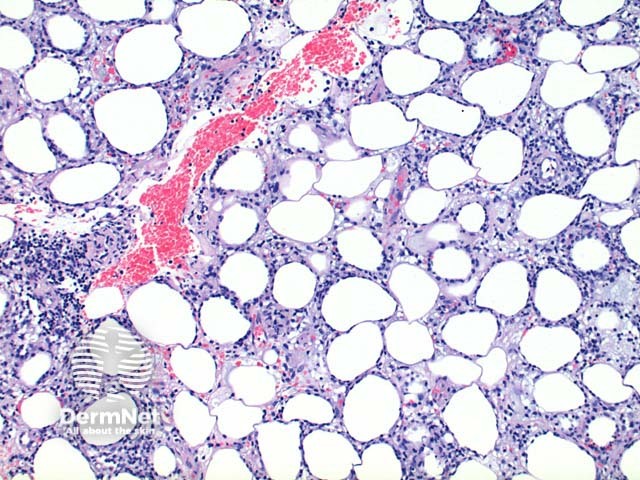

Scanning power view demonstrates lobular panniculitis (Figure 1). Relatively little dermal or epidermal involvement is seen (Figure 2). A dense infiltrate is seen predominantly within the fat lobules while some spillover into the septal panniculus may be seen (Figure 3). Germinal centre formation is rare. The infiltrate is predominantly lymphocytic with variable numbers of histiocytes engulfing nuclear debris (bean bag cells) and lipid (lipophages) (Figures 4 and 5). The lymphocytes demonstrate nuclear atypia and can be seen to characteristically rim the adipocytes (Figure 6).

Figure 2